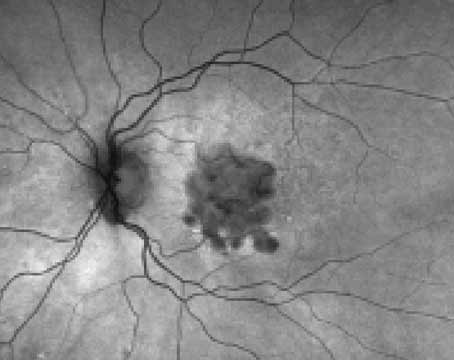

Reframing the discussion around geographic atrophy

Understanding the natural disease progression will help us talk to our patients about new and emerging treatments.